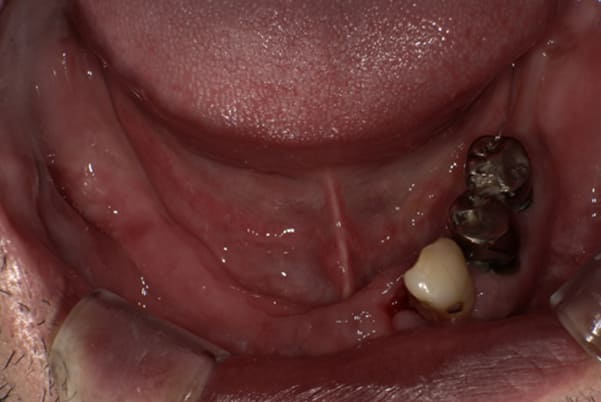

下顎治療前

-

下顎治療後

治療前の入れ歯の奥歯は、治療後の義歯と比較しても分かるように、歯が削れ平らになった状態です。

これにより奥歯のかみ合わせは低くなり、前歯のみが強くあたり、かみ合わせにより上の前歯大きな負担がかかっていたことにより、上の前歯が折れたことが考えられます。